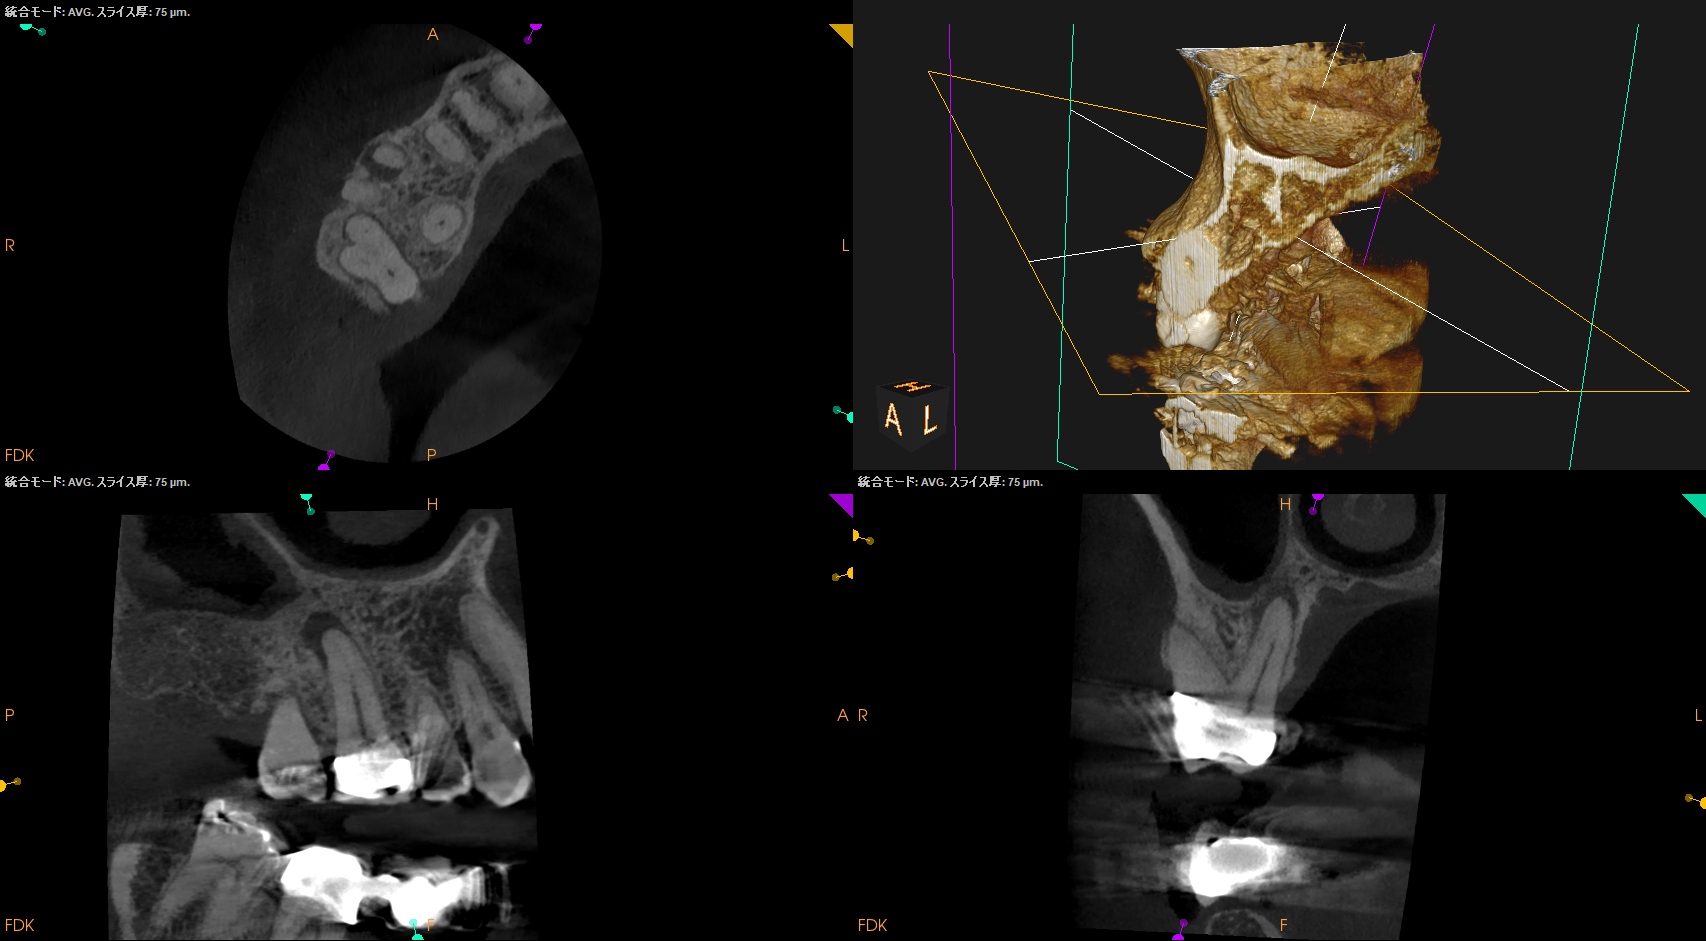

Pre-op Endo test(2025.1.27)

MB,DBのApexが歯槽骨から透けて見えている。

圧痛の原因はこれだ。

そしてSinus tract。

Pulp Dx: Pulp Necrosis

Periapical Dx: Chronic apical abscess

Recommended Tx: RCT